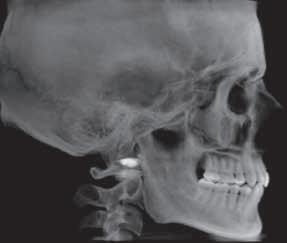

figure 1. Left, patient wearing oral appliance (OA) in neutral position. Right, patient with 2 mm of mandibular advancement. Of interest is the radiographic image of an apparent increase in pharynx size. Courtesy of Dr Trish Braga, AADSM.

their sockets” by an oral appliance. Careful explanations that do not involve contradicting the referring physician are provided. the gradual and nontraumatic advancement of the mandible is emphasized, as well as careful monitoring over a period of months by the dentist, can help reduce anxiety. Diagrams and models are then used to help the patient visualize the anatomy involved in osa and oat (see Figures 1 and 2).

figure 2. Head, neck, and mandible positions, and corresponding airway dimensions.